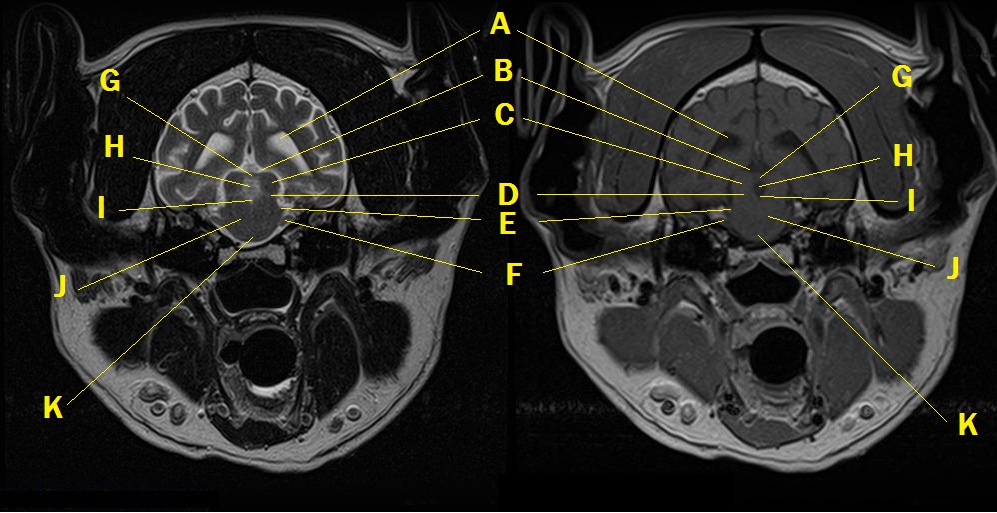

MRI anatomy 9

Q. Identify the structures labeled below:

A. lateral ventricle

B. subarachnoid space

C. caudal colliculus

D. trochlear nerve in rostral medullary velum

E. middle cerebellar peduncle

F. trigeminal nerve

G. commissure of the caudal colliculus

H. rostral cerebellar vermis and rostral medullary velum

I. 4th ventricle

J. pontine tegmentum

K. pyramid